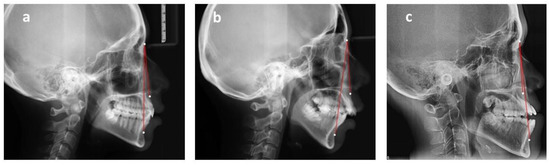

The skeletal relationship between the maxilla and mandible of orthodontic patients was categorized as Class I, Class II, or Class III [35,36,37,38] (Figure 1 and Figure 2). Steiner’s analysis [39] and Tweed analysis [40] were used for the measurements according to the analysis of St. Louis University in the United States, where the first author was trained for her orthodontic graduate program. The dental relationship between the maxilla and mandible of orthodontic patients was defined as molar Class I, Class II, or Class III (Figure 3). The DMFS index was expressed as the total number of teeth that were decayed (D), missing (M), or filled (F) in an individual with permanent dentition. There were five surfaces (facial, lingual, mesial, distal, and occlusal) for the posterior teeth and four surfaces (facial, lingual, mesial, and distal) for the anterior teeth when the DMFS index was calculated.

Figure 3. Angle’s classification of malocclusion. (a) Class I molar relationship: the mesiobuccal cusp of the upper first molar occludes the mesiobuccal groove of the lower first molar. (b) Class II molar relationship: the mesiobuccal cusp of the upper first molar occludes in front of the mesiobuccal groove of the lower first molar. (c) Class III molar relationship: the mesiobuccal cusp of the upper first molar occludes behind the mesiobuccal groove of the lower first molar.